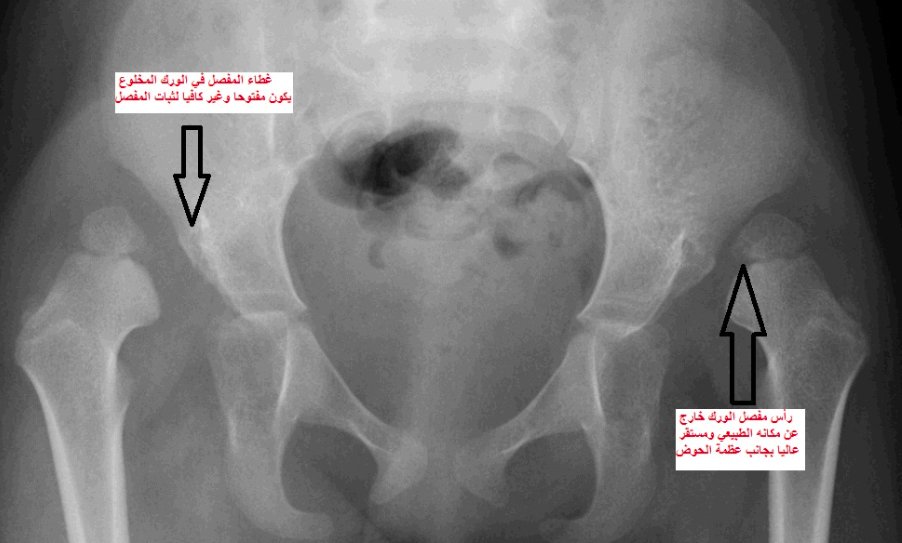

في الصورتين القادمتين تبيان لشكل مفصل الورك عند الأطفال في السنة الثانية من العمر، الأولى تبين الوضع الطبيعي لهذا المفصل الهام والثانية توضح مشكلة الخلع الولادي الكامل لمفصل الورك

الأشعة السينية الاعتيادية كالتي عرضت قبلا لأطفال في السنة الثانية من العمر لا تكون واضحة وتشخيصية لمشكلة الخلوع الولادية في الأشهر الأولى للطفل، لأن عظام الطفل في هذه السن المبكرة مازالت غير متكونة بشكل كاف يسمح بظهورها في هذا النوع البسيط من الأشعة.